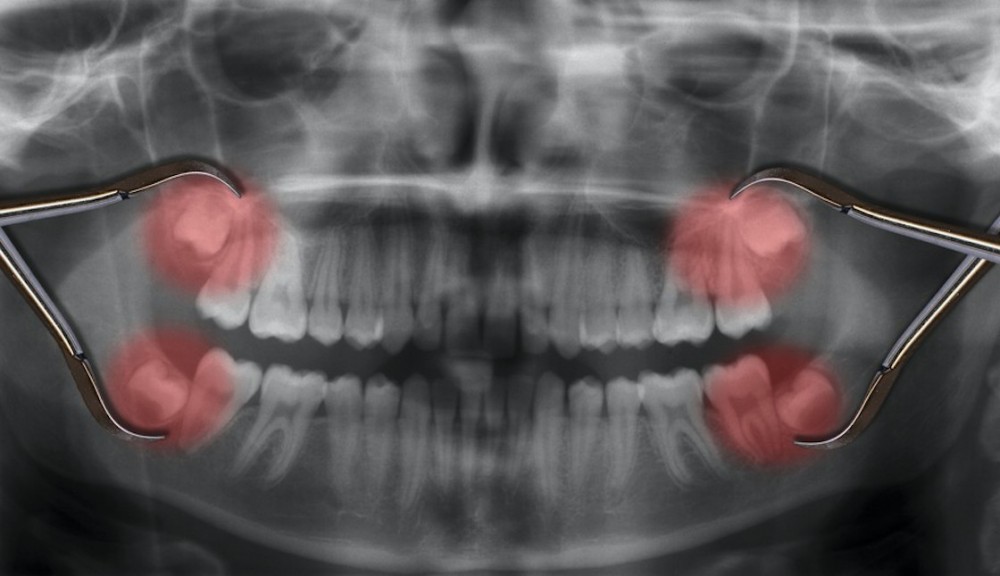

智慧齒是人類第三隻大臼齒,即是第三隻大牙,一般在十六、十七歲開始生長出來,代表一個人開始有智慧才生長出來的牙。因為智慧齒生長出來的位置比較後方,如果生長得不好,例如橫向生長、斜向生長,常見會引起蛀牙、發炎、腫痛等,有些情況更加會出現病變,形成水瘤或良性腫瘤。

根據本港衞生署資料,如果能夠保持理想的口腔衛生,或智慧齒完全給埋在牙槽骨內並沒長出,又或阻生的智慧齒沒引起不適,就可以觀察情況及作定期檢查以防病變。如果「阻生智慧齒」反覆出現不適或引起嚴重問題,就可能要把它拔掉。

聽到要剝智慧齒,一般人也會擔心疼痛,到底剝智慧齒的過程是怎樣?有些情況,智慧齒的牙根是位於頜骨深處,並接近主要神經線,拔牙手術就可能對神經組織造成傷害,引致口部麻痺並失去感覺。

因此要按臨床情況、牙科醫生的診斷、病人的意願,並要平衡拔牙的益處和風險,才決定是否拔除或何時拔除「阻生智慧齒」。手術一般會在局部麻醉情況下進行,有時可能會在全身麻醉或施以鎮靜劑的情況下進行。正常情況下,拔牙過程是無痛的。